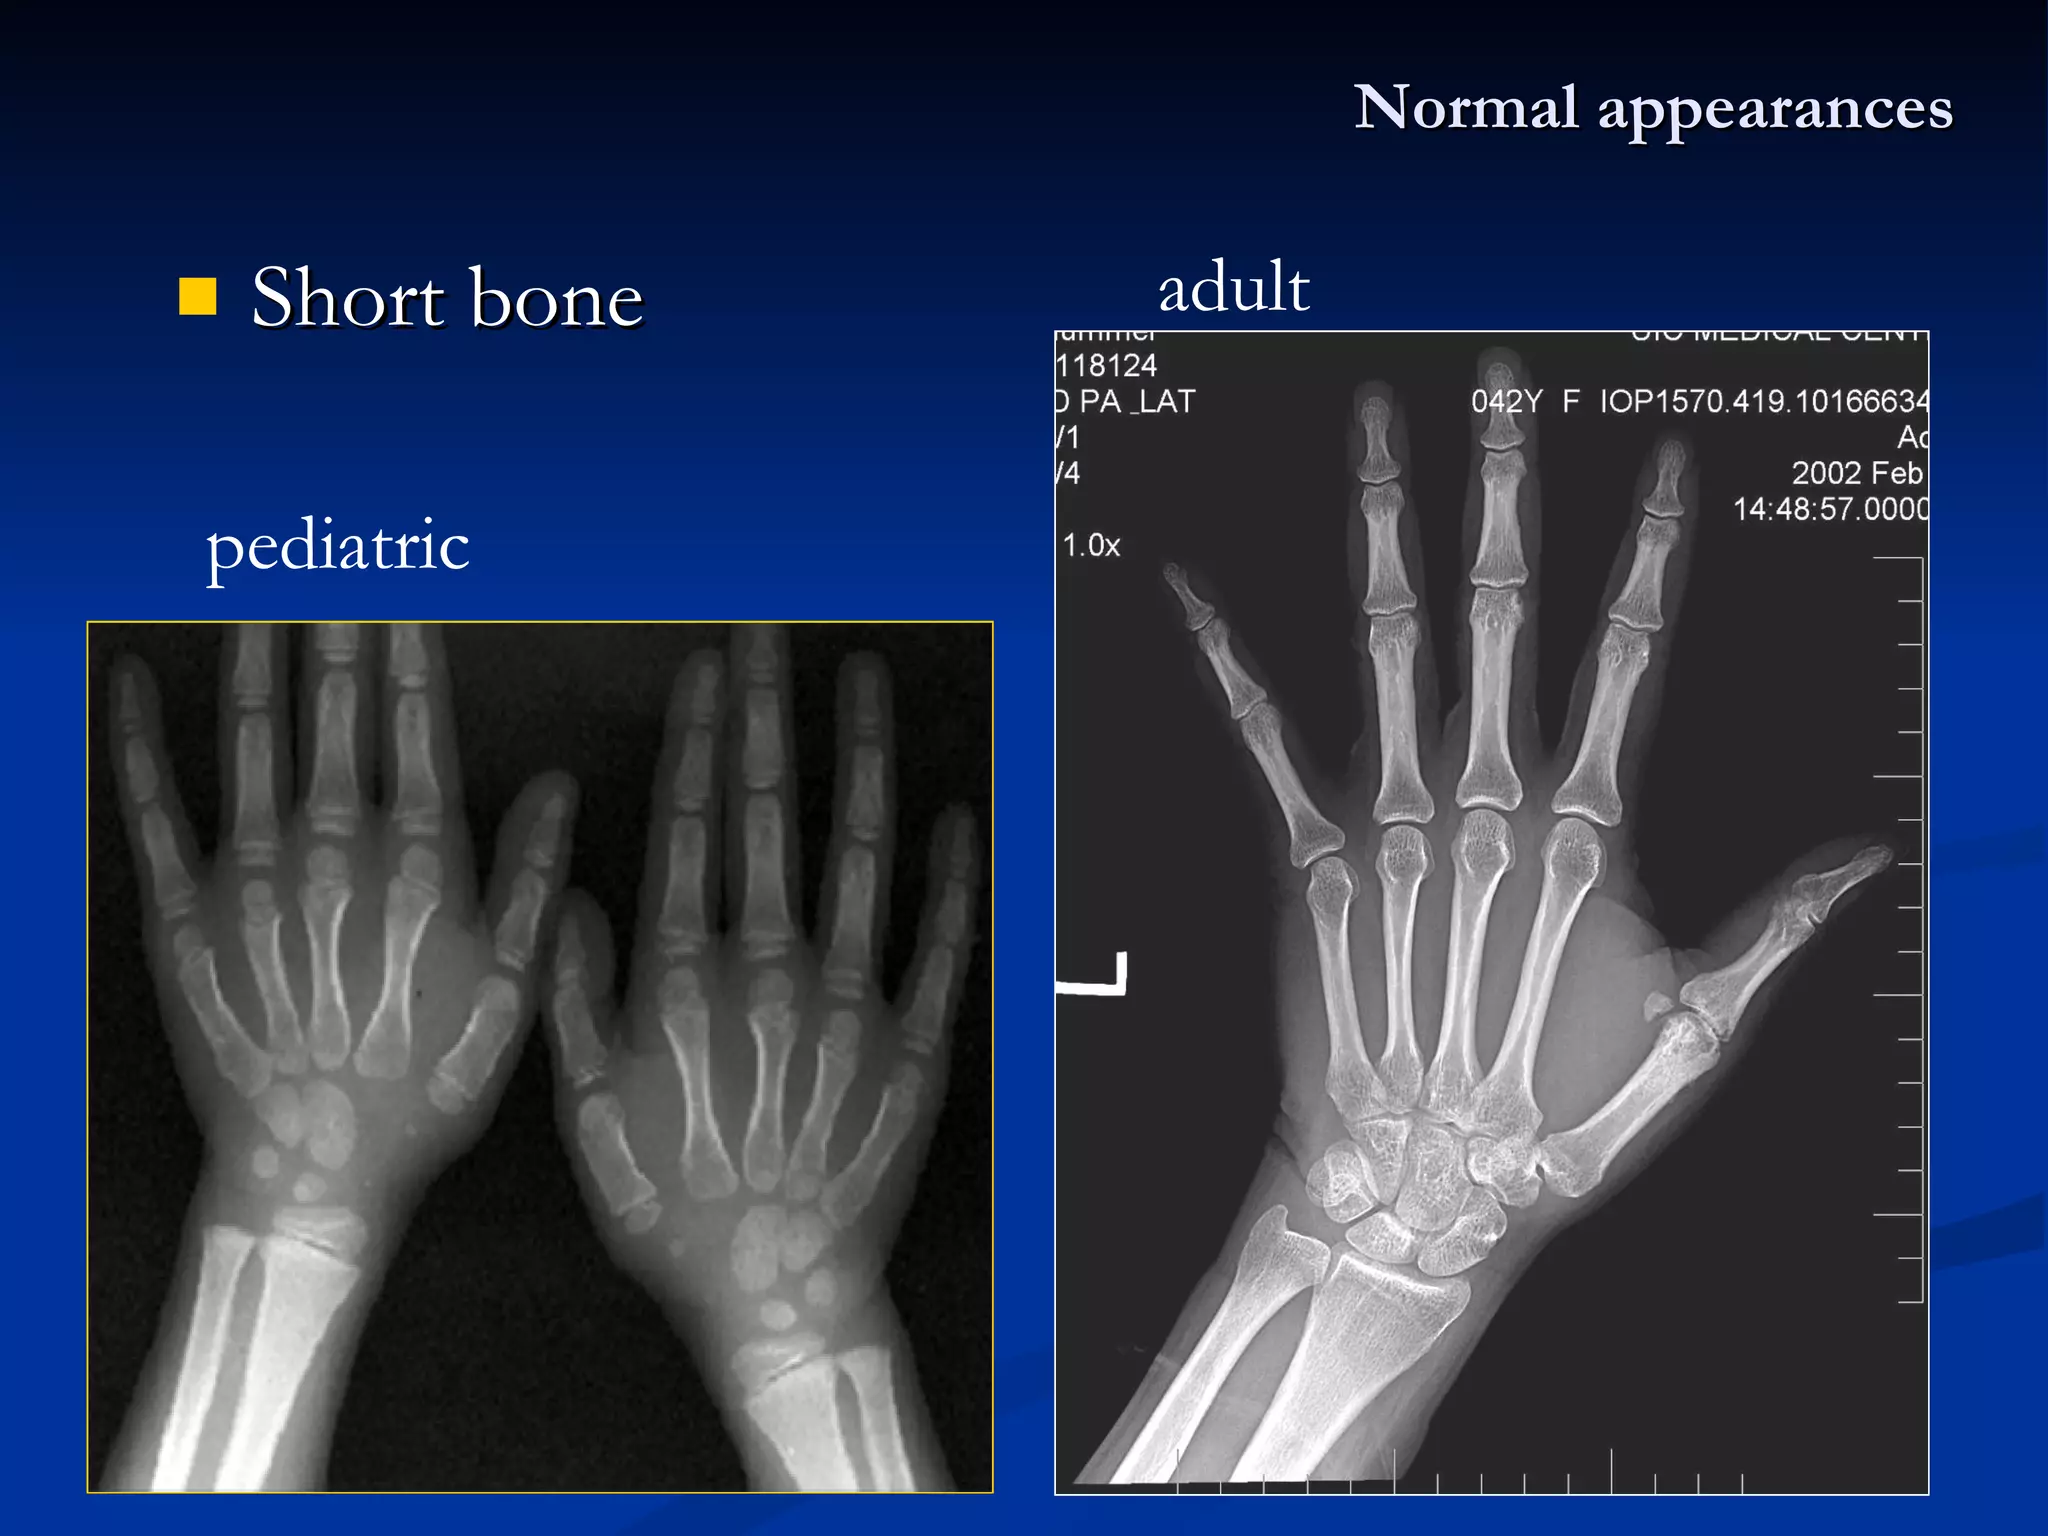

Short bone Normal appearances pediatric adult

Normal X-ray appearancesThe types of skeleton: Long bone Pediatric : diaphysis 、 metaphysis 、 epiphysis 、 epiphyseal plate Adult : diaphysis (shaft) 、 Short bone Flat bone – hematopoiesis Irregular bone Joint

Short bone Normalappearances pediatric adult